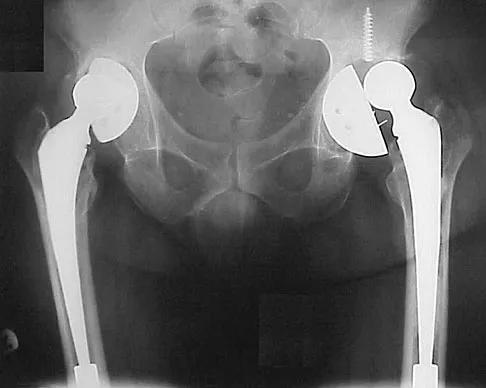

Master AAOS & ABOS boards with high-yield practice MCQs for Set 2. Covers hip and knee reconstruction, includ…

High-yield MCQs for Set 1 on Hip & Knee Reconstruction, perfect for AAOS & ABOS board review. Covers arthropl…